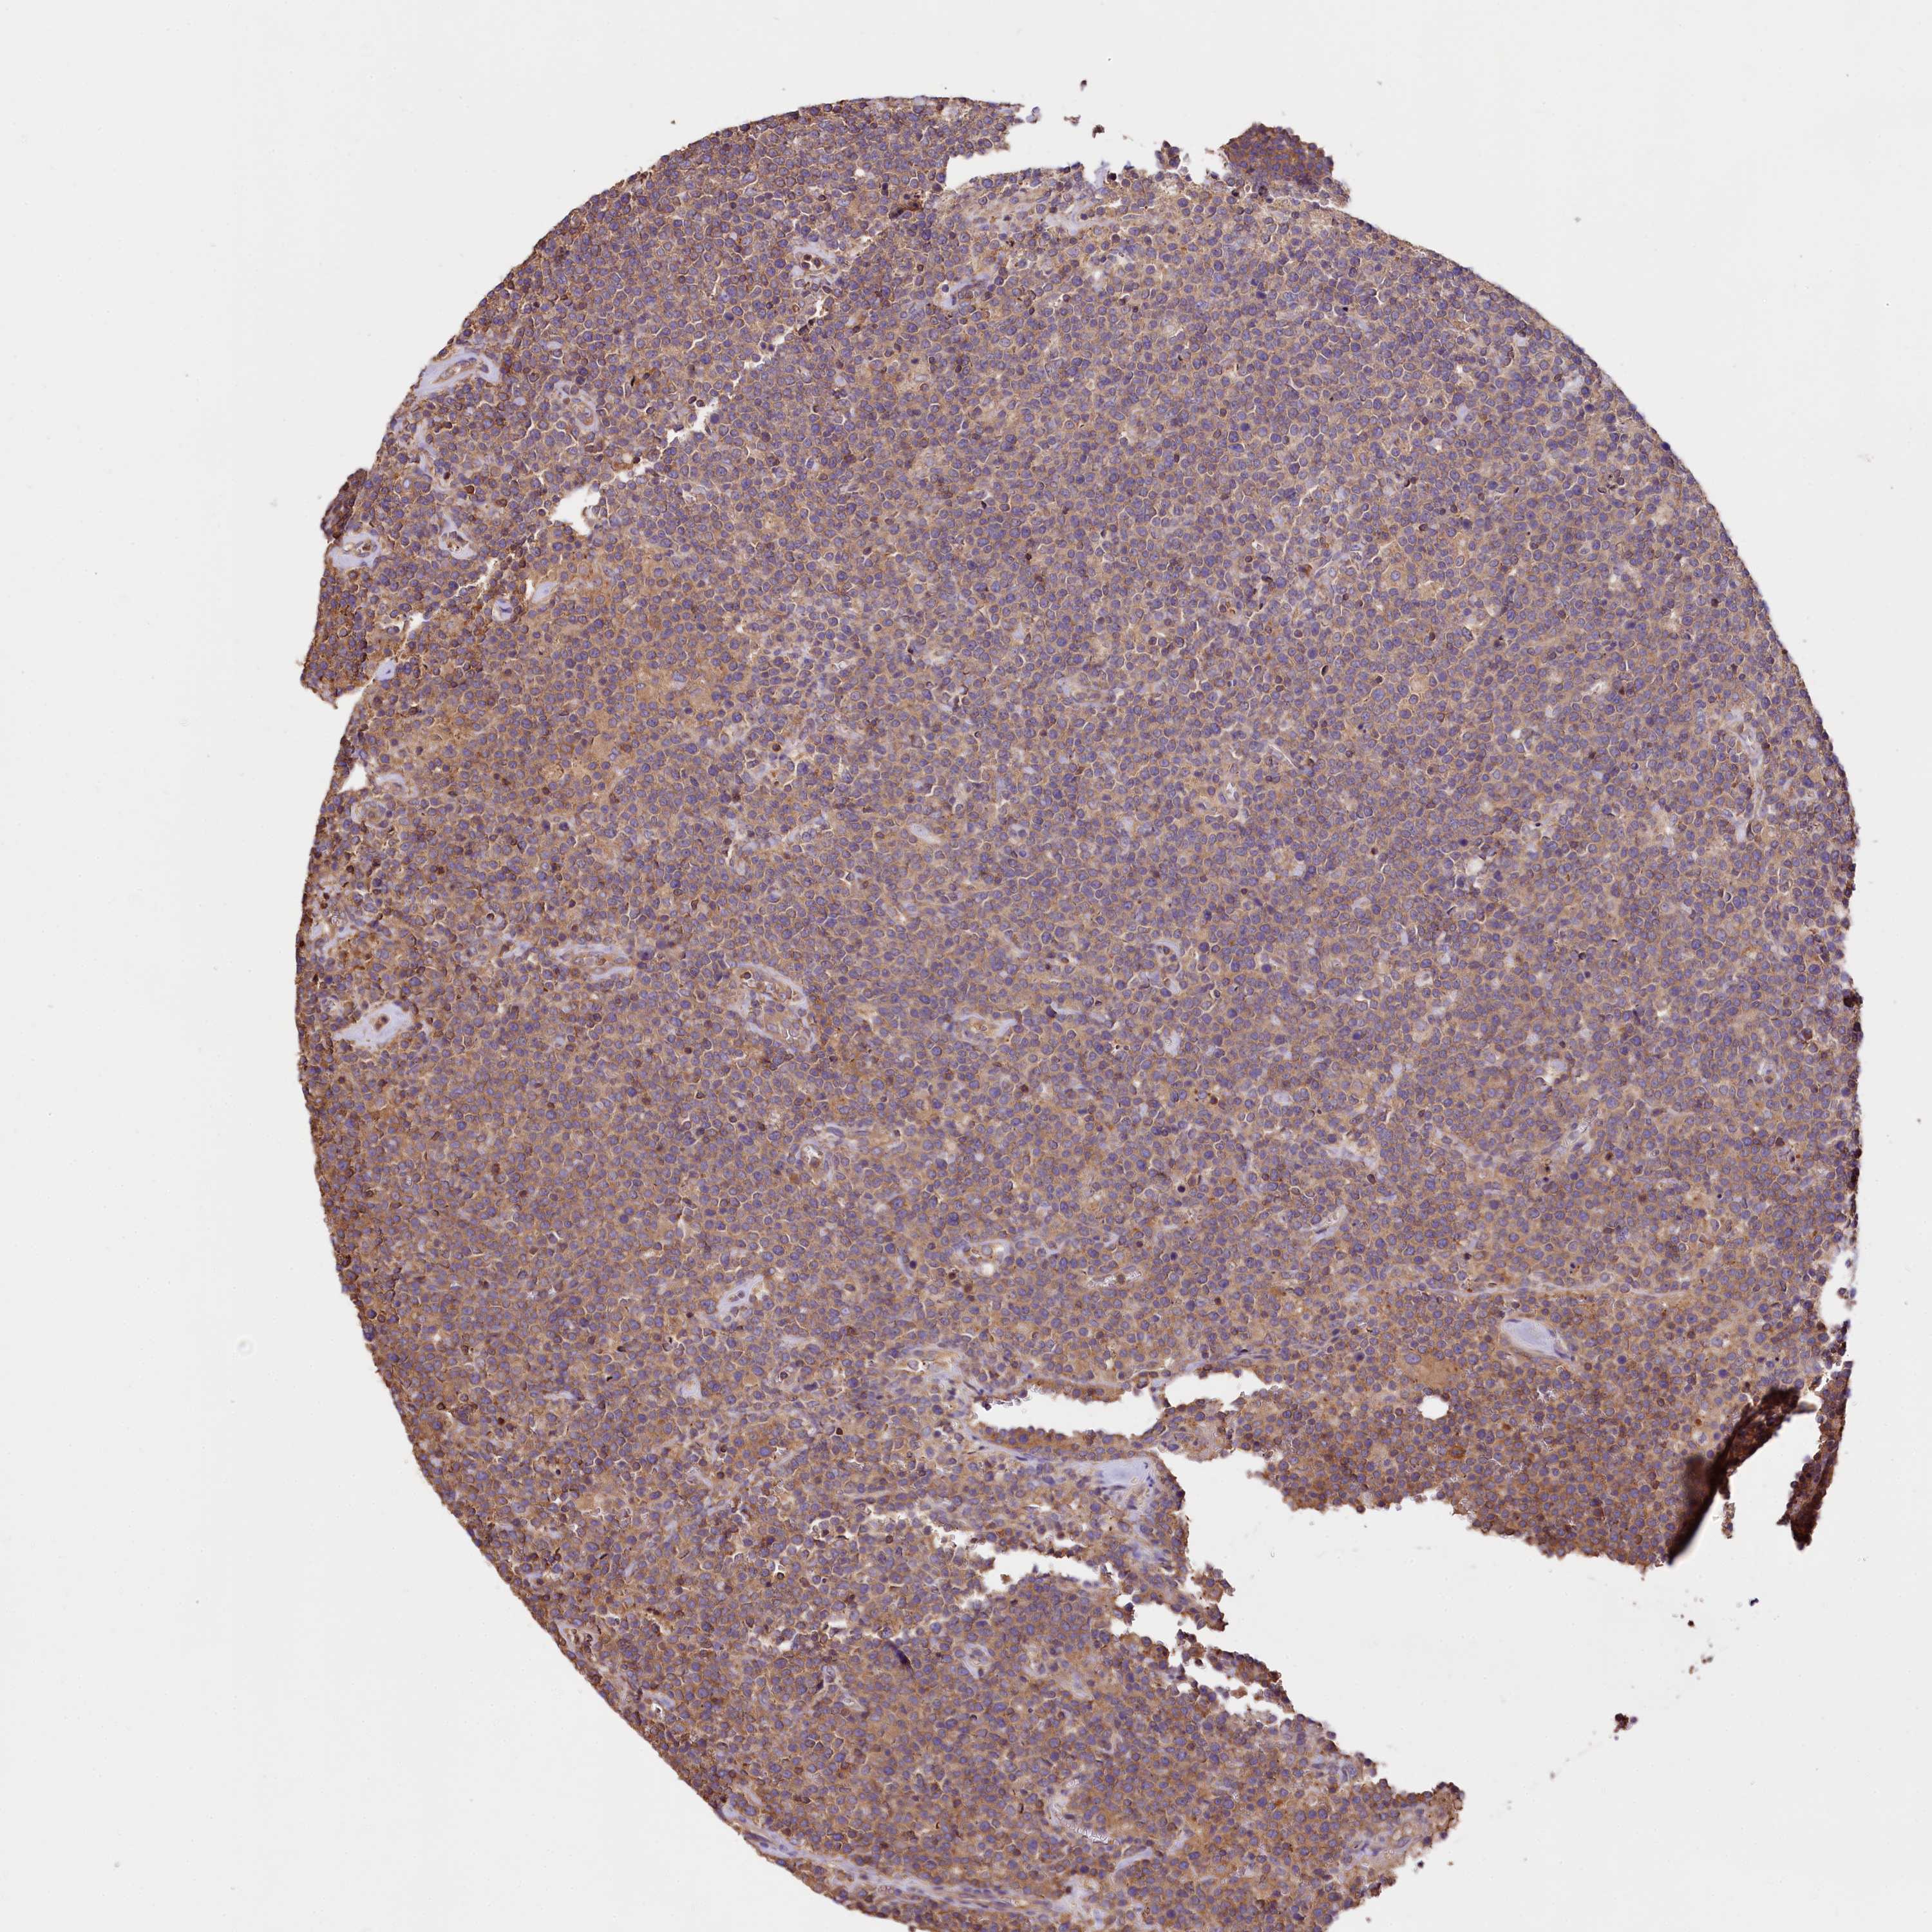

CANCER LYMPHOMA Show tissue menu

LYMPHOMA - Protein expressioni

A mouse-over function shows sample information and annotation data. Click on an image to view it in a full screen mode. Samples can be filtered based on level of antibody staining by selecting one or several of the following categories: high, medium, low and not detected. The assay and annotation is described here.

Each image is clickable and will lead to virtual microscopy that enables deeper exploration of all samples and also displays staining intensity scores, fraction scores and subcellular localization as well as patient and tissue information for each sample.

Antibody HPA039987

Antibody HPA042645

Staining

High

Medium

Low

Not detected

Intensity

Strong

Moderate

Weak

Negative

Quantity

>75%

75%-25%

<25%

None

Location

Nuclear

Cytoplasmic/membranous

Cytoplasmic/membranous,nuclear

Hodgkin's disease, NOS

Malignant lymphoma, non-Hodgkin's type, High grade

Malignant lymphoma, non-Hodgkin's type, Low grade